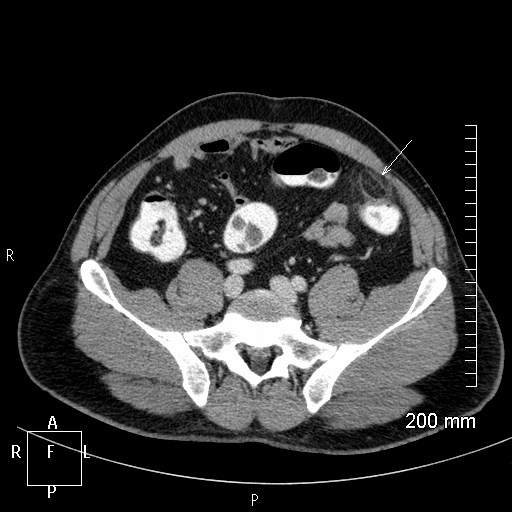

Le patient a une diverticulite. Devant persitance fièvre et augmentation du sd inflammatoire à 48h on réalise le TDM suivant. Vu la taille de l’abcès (>5 cm on va dire), quelle CAT?

drainage de l’abcès: ponction percutanée écho ou scanno-guidée; OU drainage chirurgical si percut impossible (avec RDC à distance)